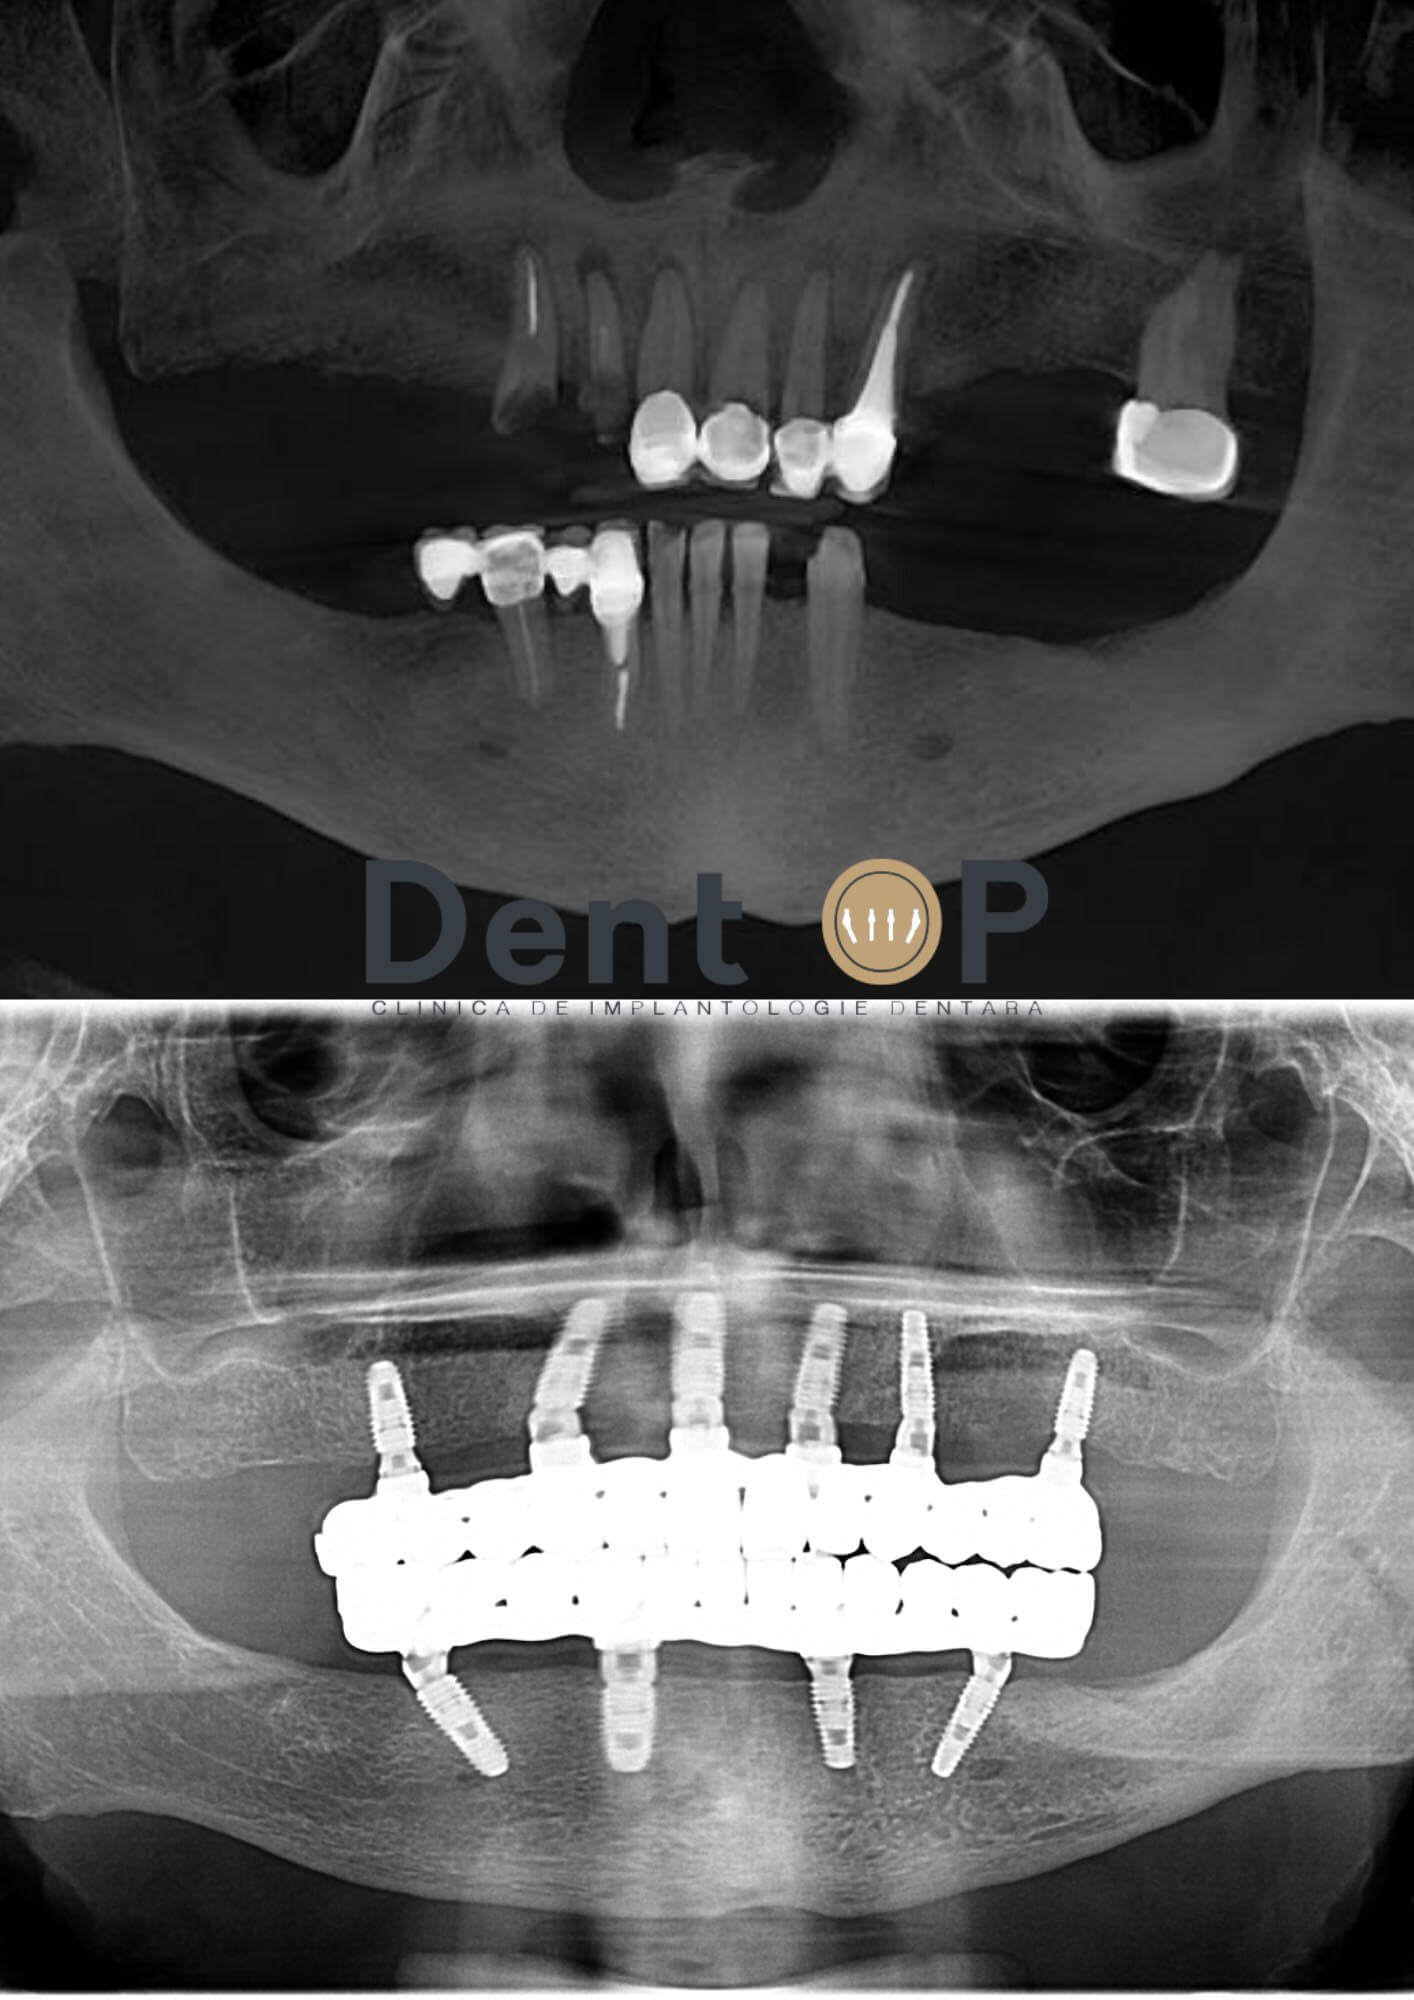

Domnul I. s-a prezentat la clinică cu o serie de lucrări vechi, care pe dedesubt au prezentat mai multe carii. Din acest motiv funcționalitatea masticatorie a pcientului s-a diminuat, iar aspectul danturii sale a început să devină unul neplăcut.

În cadrul consultației alături de Dr. Cazacu Corrado- Medic Specialist Chirurgie Dento-Alveolară s-a stabilit reabilitarea danturii pacientului cu ajutorul a 6 implanturi la maxilar și 4 la mandibulă după extracția lucrărilor vechi. Acestea au putut fi realizate cu ajutorul procedurii de Sedare Conștientă, care l-a ajutat să se simtă relaxat pe parcursul intervenției și să nu simtă durere.

După 24h , pacientul a primit lucrările provizorii, care l-au ajutat temporar să mănânce și să aibă o dantură frumoasă. După cele 4-6 luni, pacientul s-a prezentat pentru inserarea lucrărilor finale.